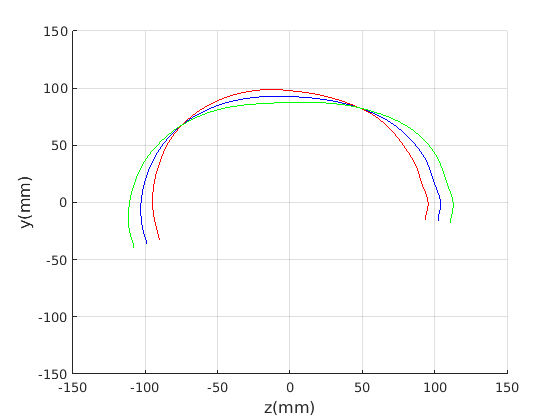

Figure 16 shows examples of the robust ellipse fit for four head profiles. The centre of the ellipse is used in a pose normalisation procedure where the ellipse centre is used as the origin of the profile and the angle from the ellipse centre to the nasion is fixed at -10 degrees. We call this Ellipse Centre - Nasion (ECN) pose normalisation and later compare this to GPA. The major and minor axes of the extracted ellipses are plotted as red and green lines respectively in Fig. 16.

|

Figure 17 shows all 100 profiles overlaid with the same alignment scheme. The median value of major ellipse axis and the ellipse centre-nasion angle differ by 3.6 degrees, so that when the nasion angle is fixed at -10 degrees, the median ellipse angle is -6.4 degrees (cf. -7.4 degrees with manual landmarking of the nasion). We noted regularity in the orientation of the fitted ellipse as is indicated by the clustering of the major (red) and minor (green) axes in Fig. 17 and the histogram of ellipse orientations in Fig. 18. For most people, the major axis of the ellipse is closely aligned with the y-axis (upright), and titled slightly forwards. A minority of heads (9%) in the training sample have their major ellipse axes closer to the vertical (these relatively tall and short heads are known as brachycephalic.) Ellipse axis clustering (relative to the fixed ellipse centre-nasion line) does not appear to be sharply defined. This is because many crania are close to circular in cross-section, making the orientation of these angles sensitive to small changes in shape from one person to the next. Note also the variation at the back of the head due to a variety of hair styles, some of which protrude from under the cap. We limit the region over which we model the cranial shape in order to crop this unwanted data out.